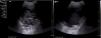

A diagnosis of MPE due to stage IV kidney cancer was made, and in view of the persisting pleural effusion, we decided, after explaining the different therapeutic alternatives to the patient, to place a TPD catheter (IPC™ Rocket Medical©, Watford, United Kingdom), and both the patient and his family members were instructed how to perform drainage at home. About 30 days after TPD placement, the patient attended the clinic with dyspnea on minimal effort (visual analog scale [VAS]: 8/10, modified Medical Research Council dyspnea grade: III), with ineffective TPD draining. Chest X-ray revealed grade II/IV right pleural effusion, unchanged from previous studies, with the catheter placed correctly in the right hemithorax. A chest ultrasound showed grade II/IV effusion containing multiple septa and detritus (Fig. 1A). An intrapleural instillation of 100000IU urokinase was administered and left to act for 2h, after which chest ultrasound was repeated, according to our protocol; this showed total lysis of the septa and persistent pleural effusion with detritus (Fig. 1B). This effusion was drained, obtaining 750ml of serosanguineous fluid; no associated complications were reported, and the patient showed significant symptomatic relief.

Patient, 61 years of age, with malignant pleural effusion due to stage IV kidney cancer, presenting with non-draining tunneled catheter. Chest ultrasound showing abundant septa preventing drainage of pleural fluid (A). A single dose of 100000IU urokinase was instilled and left to act for 2h; the thoracic ultrasound was then repeated, revealing pleural effusion containing detritus and lysis of the septa (B). The effusion was than drained, obtaining 750ml of serosanguineous pleural fluid and subsequent symptomatic improvement.